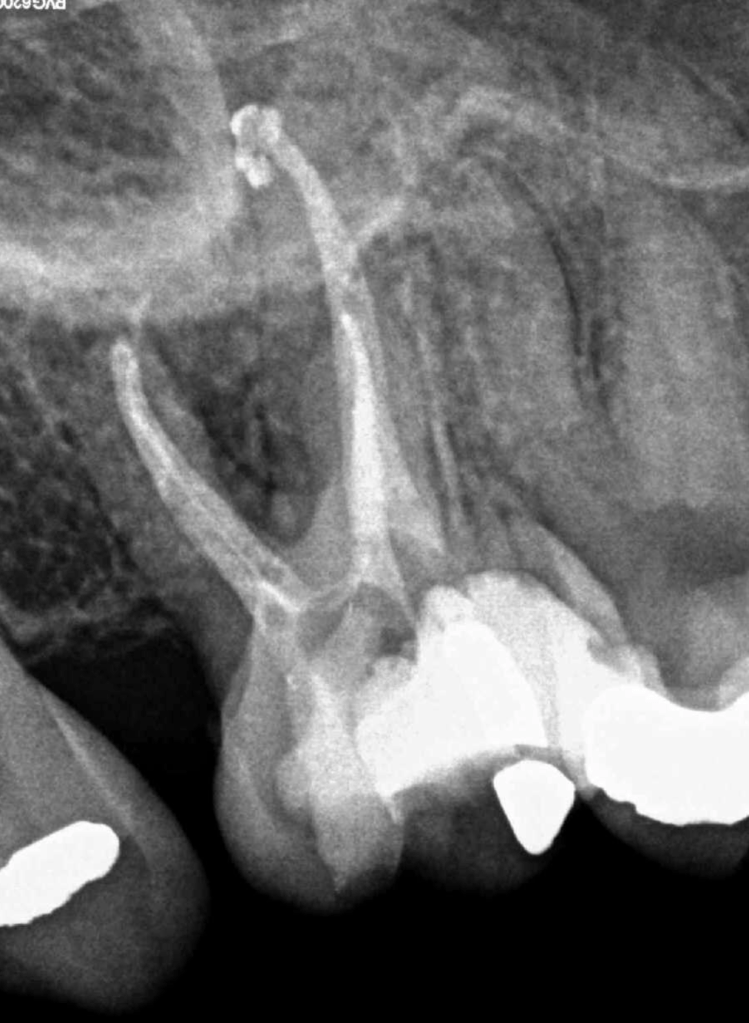

Retratamiento Primer Molar Superior